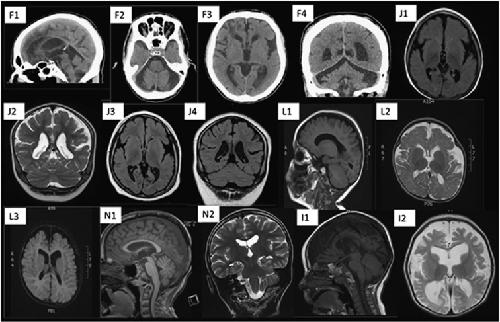

De novo and inherited mutations in the X-linked gene CLCN4 are associated with syndromic intellectual disability and behavior and seizure disorders in males and females.,

Palmer EE,Stuhlmann T,Weinert S,Haan E,Van Esch H,Boyle J,Leffler M,Moraine C,van Bokhoven H,Kleefstra T,Kahrizi K,Najmabadi H,Sirsi D,Golla S,Sommer A,Pietryga MP,Chung WK,Wynn J,Rohena L,Hamlin D,Faux BM,Grange DK,Manwaring L,Tolmie J,Joss S,Cobben JM,Goehringer JM,Challman TD,Hennig F,Fischer U,Grimme A,Suckow V,Musante L,Nicholl J,Shaw M,Niu Z,Rosenfeld JA,Jentsch TJ,Gecz J,Field M,Kalscheuer VM,Lodh SP,Stankiewicz P,Raynaud M,Delgado MR,Bernardo E,Duijkers FAM,Holvoet M,Ropers HH,

Mol Psychiatry. February 1, 2018; 23(2):1476-5578.